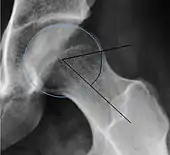

| Alpha angle | ![]() |

Degree of bulging of the femoral head-neck junction: In normal conditions there is a symmetric concave contour at the junction of the femoral head and neck. Loss of this concavity or bone bulging may lead to cam type impingement. The degree of this deformity can be measured by the alpha angle. Although it can be measured in the cross-lateral view, the 45° Dunn view is considered more sensitive and the frog leg view more specific in determining pathologic values. |

|